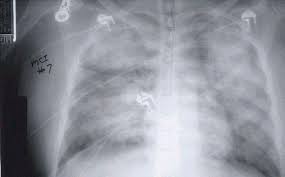

• Radiografía de tórax